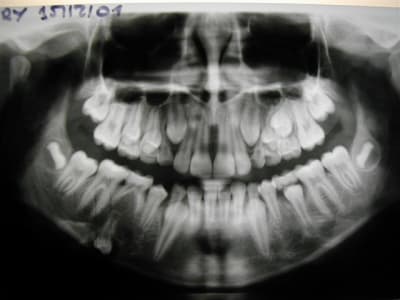

la conclusion à tirer serait qu'on ne fait peutêtre pas assez de pano systematique sur les gamins à 7/8 ans pr voir où st les germes

et il y a de plus en plus d'agenesies j'ai l'impression par rapport à il y a 20 ans(ou je faisais moins de pedo?)

cela permet aussi de voir les angulations des canines,le manque de place et intercepter en envoyant en odf

hier encore gamine de 6 ans1/2:agenesie des 4 2è PM permanentes

sinon on peut se retrouver avec des suprises...

(nina vue à 11 ans)